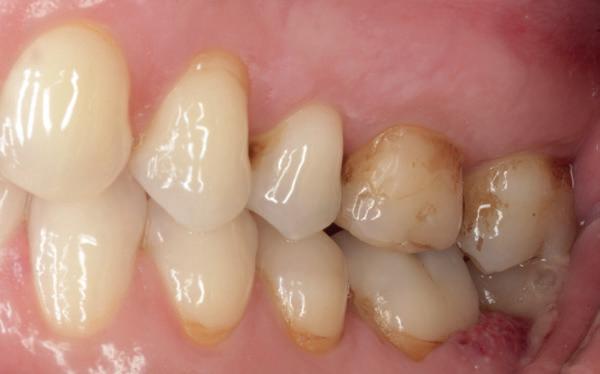

1. Studiofoto intake

aan zijn gebit gedaan behalve pappen en nathouden. Tandheelkundige zorg werd enkel verleend wanneer er zich een probleem voordeed (afbeelding 1, 3, 5).

De patiënt werd in de eerste fase gezien door de parodontoloog, implantoloog en restauratief behandelaar. Klinisch werden drie complicerende factoren vastgesteld: inadequate mondhygiëne, een ongunstige occlusale relatie en restauraties met gebrekkige marginale adaptatie met overhang. De patiënt werd opgenomen in het parodontale behandelprotocol.

De diagnose luidde lokaal parodontitis met ernstige furcatie aandoeningen; Stadium IV (vergevorderd); graad C (snel progressief) (afbeelding 7) De elementen die niet te behouden waren, werden geëxtraheerd.